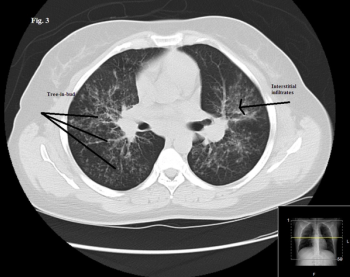

Worsening respiratory symptoms and fatigue of 6 months’ duration brought a 44-year-old woman in for evaluation. Diagnosed with asthma 2 years earlier, she was compliant with, but unresponsive to treatment. Your impressions?

Re-expansion pulmonary edema is noncardiogenic and follows re-expansion of the lung after thoracentesis is performed for large amounts of pleural effusion or for pneumothorax.